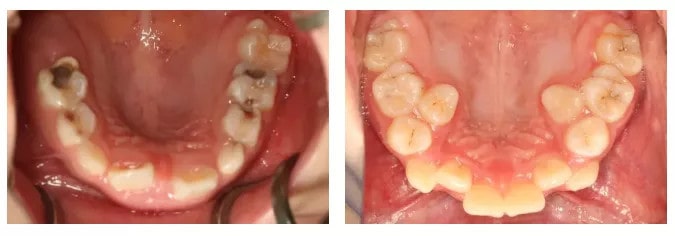

龋病俗称“虫牙”、“蛀牙”,发生在儿童乳牙时期的龋病称乳牙龋病,是一种细菌性疾病,具有发病早、患龋率高、龋蚀发展速度快等特点。

乳磨牙的牙冠比继承恒牙的牙冠宽。而且乳牙的窝沟类型较为复杂,导致它更容易造成食物残留和菌斑集聚,不容易清洁干净。

浅龋

病变只存在于牙齿表层一般情况没有龋洞和主观症状。釉质上会有白垩色的点或斑,后面会逐渐变成黄褐色或褐色斑点。

中龋

龋蚀已达到牙本质浅层,形成浅层龋洞孩子会开始对冷热酸甜的食物出现敏感症状。

深龋

龋蚀已达到牙本质深层接近牙髓,或已影响牙髓对冷、热、酸、甜都有明显痛感,对热尤其敏感。这时候大多要进行牙髓治疗以保存牙齿。

浅龋中龋深龋儿童大概在两岁半的时候长齐乳牙,12岁左右乳牙基本会全部换为恒牙。乳牙的使用时间可不短呢。